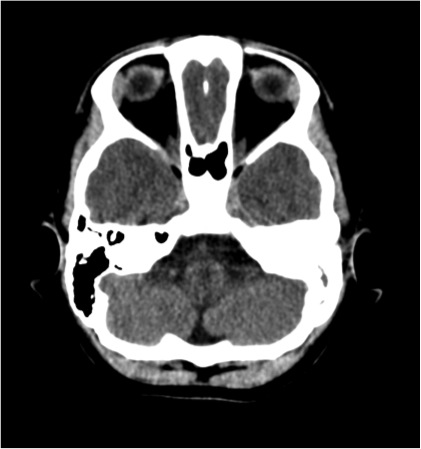

All�arrivo in reparto viene avviata analgosedazione con fentanyl e midazolam in infusione continua e proseguita la terapia antibiotica. Eseguita TC encefalo con riscontro di otomastoidite sinistra e sinusite cronica; puntura lombare con fuoriuscita di LCR torbido a goccia rapida ed EEG compatibile con quadro di sofferenza cerebrale diffusa.

In terza giornata vengono eseguiti ulteriori approfondimenti diagnostici quali RM encefalo, angio-TC e TC delle rocche petrose che confermano un quadro di sofferenza cerebrale diffusa con coinvolgimento flogistico di aree cerebrali multiple (temporale, fronto-parietale, occipitale, emisferi cerebellari e nuclei della base), e otomastoidite con erosione delle pareti ossee delle celle mastoidee (Figura 1 e Figura 2). I tracciati EEG seriati hanno documentato un peggioramento progressivo, fino al riscontro di assenza di attivit� elettrica cerebrale in sesta giornata di ricovero.

Figura 1. RM dell'encefalo.